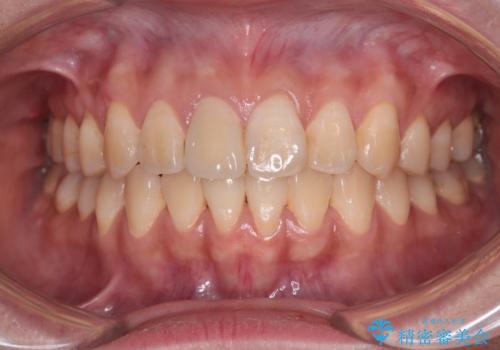

上下の八重歯とクロスバイト ワイヤー装置での抜歯矯正

上下ともに八重歯が顕著であり、前歯のクロスバイトがあったため、上下左右の第一小臼歯4本を抜歯し、ワイヤー装置での抜歯矯正を行うこととしました。

前歯の歯列が整ったことで、歯磨きが大変やりやすくなり、患者様には大変満足していただけました。